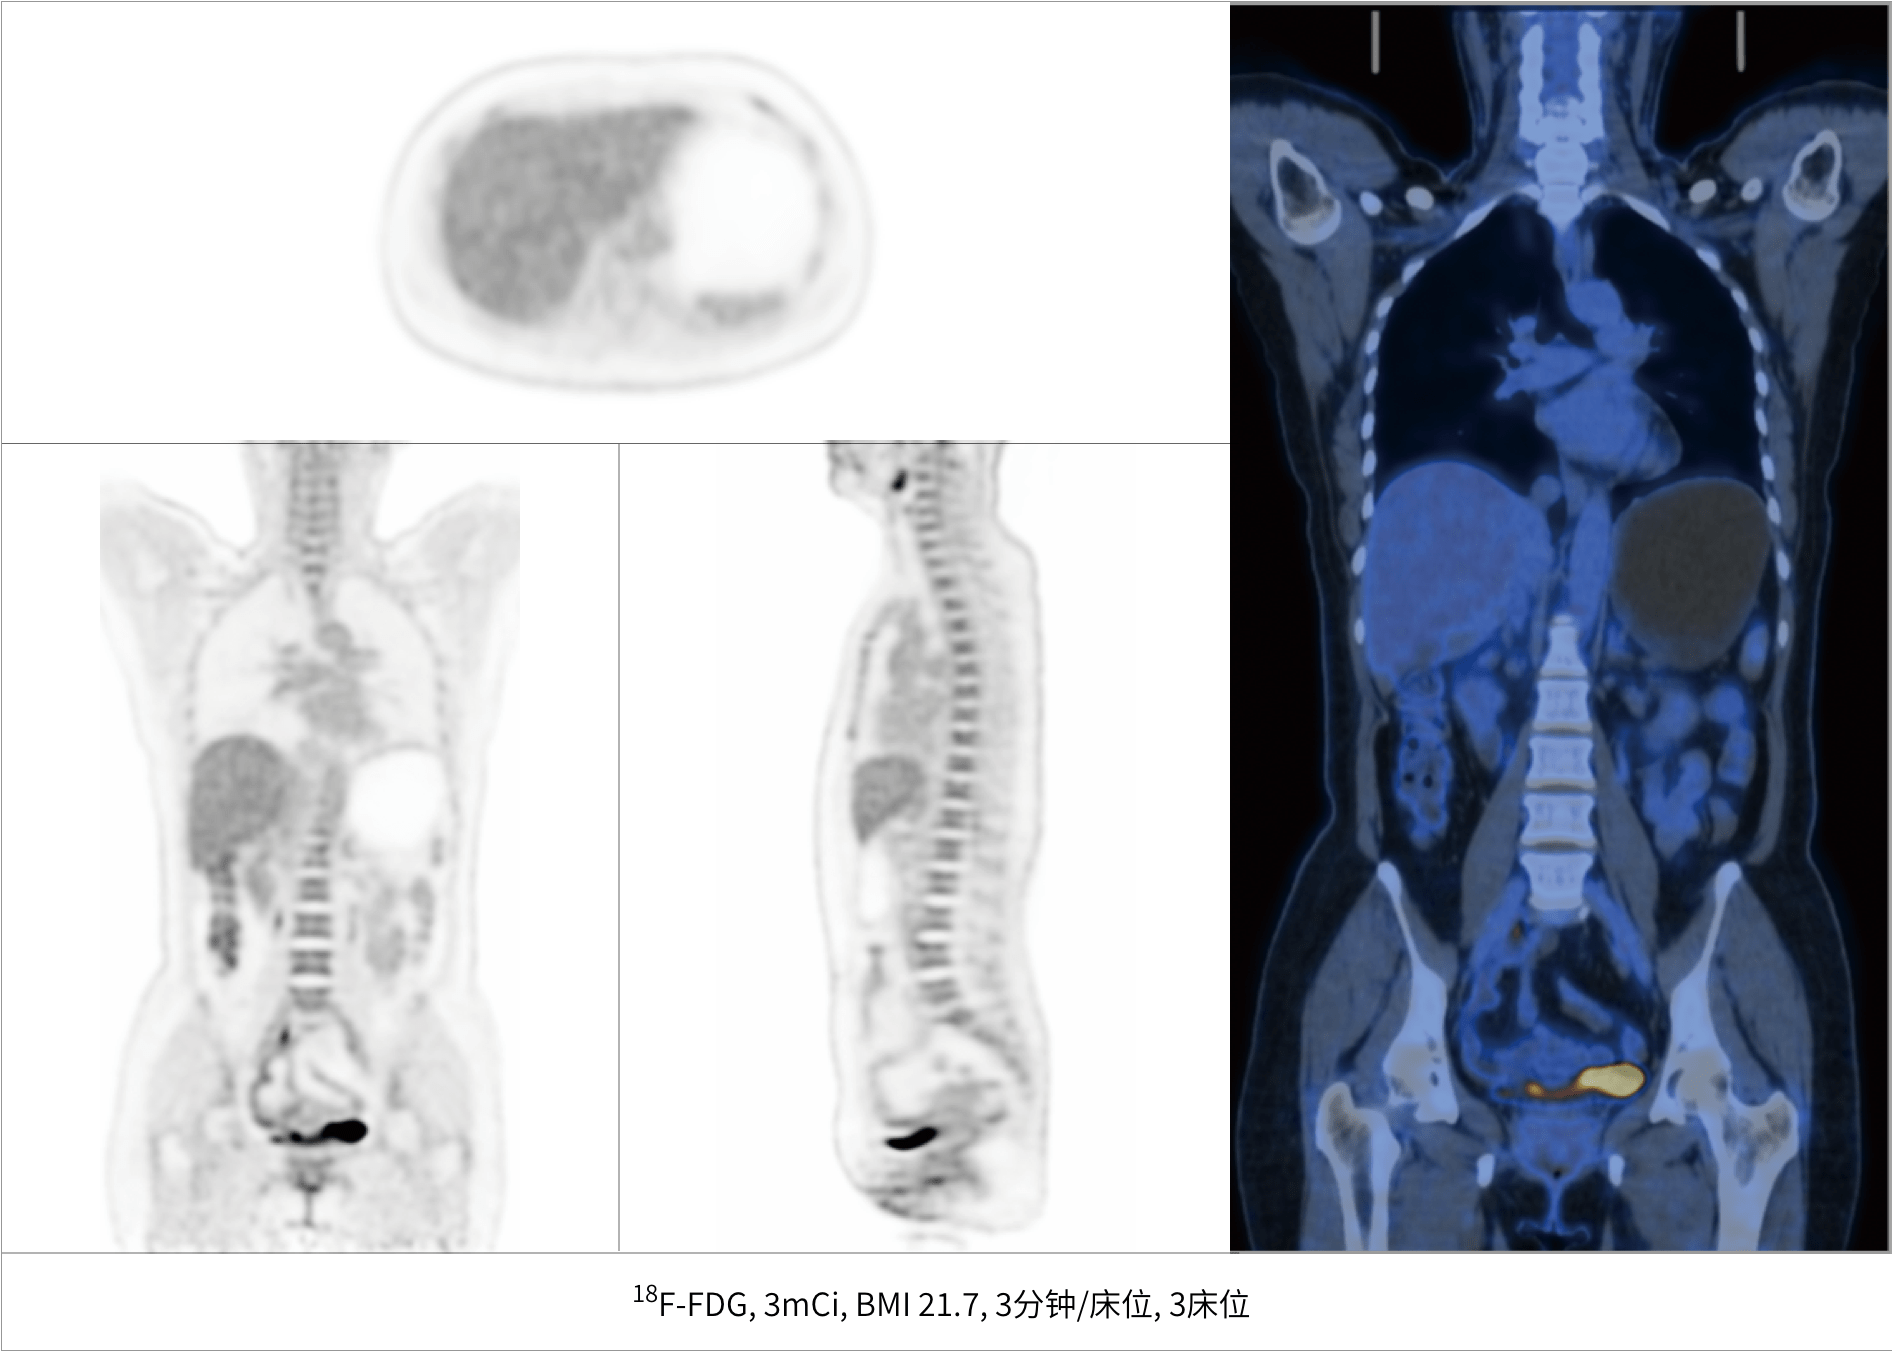

超清显像

超清NEMA分辨率成像

TOF + PSF

微小病灶无以遁形

600 x 600

超大矩阵,高精度超清重建